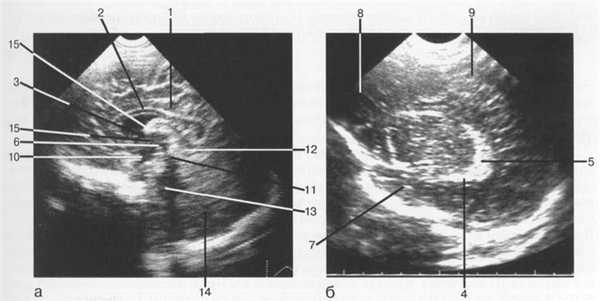

Рис. 1.1. Нейросонография. Изображения головного мозга в сагиттальной плоскости: а — срединно-сагиттальный срез; б — парасагиттальный срез через тела боковых желудочков.

I — поясная борозда; 2 — мозолистое тело; 3 — межжелудочковое отверстие; 4 — сосудистое сплетение нижнего рога; 5 — клубок сосудистого сплетения; 6 — III желудочек; 7 — височная доля; 8 — лобная доля; 9 — теменная доля; 10 — инфундибулярный карман; 11 — водопровод среднего мозга; 12 — четверохол-мная цистерна; 13 — IV желудочек; 14 — мозжечок; 15 — межталамическая спайка.